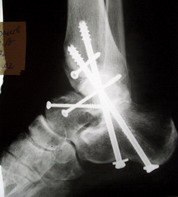

Среди повреждений таранной кости (Hawkins III-IV) с одновременной травмой лодыжек встретилось следующее (см. вложение). Пациент упал в колодец на глубину 10 метров (Х.2002 г.), госпитализирован с диагнозом: з/перелом шейки правой таранной кости (Hawkins IV) с переломовывихом тела назад и кнутри, закрытый перелом внутренней лодыжки и переднего края большеберцовой кости. Оперирован в первые 12 часов после травмы, выполнена открытая репозиция таранной кости, внутренним и передне-внутренними доступами, остеосинтез переломов шейки и тела губчатыми винтами, для реваскуляризации тела таранной кости первичный компрессионный над- и подтаранный артродез. Синтез внутренней лодыжки губчатым винтом. Удаление винтов через 1 год,2 мес. Получен анкилоз указанных суставов с сохранением длины конечности, полная реваскуляризация таранной кости, о чем говорит сращение ее переломов, отсутствие отеков и

цианоза стопы и голени. Компенсаторная подвижность переднего и среднего отделов стопы около 15-20 градусов за счет поперечного (Шопара) сустава стопы. Считаю оправданной подобную тактику, не смотря на угрожаемый прогноз (100% асептический некроз) по классифицкации Hawkins.